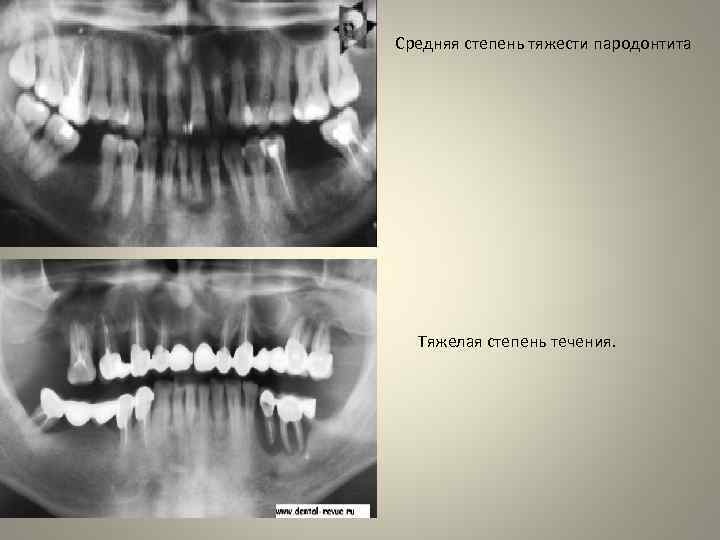

Средняя степень тяжести пародонтита Тяжелая степень течения.

• • • • В соответствии с тяжестью клинических проявлений выделяют пародонтит легкий, средней тяжести и тяжелый. Такое деление удобно для выбора вида хирургического, ортопедического вмешательств и всей комплексной терапии в целом. Для легкого пародонтита характерны: глубина пародонтального кармана до 3, 5 мм, преимущественно в области межзубного промежутка; начальная степень деструкции костной ткани по рентгенограмме (отсутствие компактной пластинки на вершине и боковых отделах перегородки, очаги остеопороза, расширение периодонтальной щели в пришеечной области); зубы неподвижны, не смещены; общее состояние пациента не нарушено. При пародонтите средней степени тяжести: глубина пародонтального кармана достигает 5 мм; имеет место резорбция костной ткани по рентгенограмме на одну треть или на половину межзубной перегородки; подвижность зубов I II степени с возможным смещением их. Тяжелая степень пародонтита характеризуется: глубиной пародонтальных карманов более 5 6 мм; деструкцией костной ткани альвеолярного отростка более, чем на половину или полным отсутствием костной ткани; патологической подвижностью зубов преимущественно II III степе ни, их смещением, выраженной травматической артикуляцией.

• Панорамная увеличенная рентгенография и ортопантомография позволяют более объективно оценивать состояние костной ткани альвеолярных отростков челюстей при заболеваниях пародонта, чем метод внутриротовой рентгенографии. При пародонтите на рентгенограмме отмечаются воспалительные изменения (резорбция) костной ткани. Они начинаются с поражения кортикальных пластинок и, прогрессируя, сопровождаются нарушением губчатой кости, нередко с образованием костных карманов. Пародонтоз характеризуется появлением на рентгенограмме склеротических изменений костной ткани челюстей; высота межальвеолярных перегородок может быть равномерно снижена. Для получения полноценной рентгенологической картины при отсутствии ортопантографа должно быть произведено не менее 4— 6 снимков